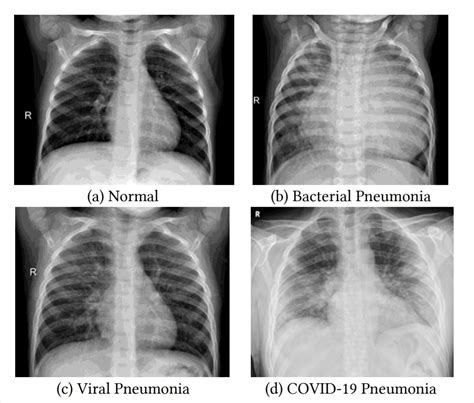

Diagnosing pneumonia typically involves a physical examination, chest X-ray, and sometimes blood tests or sputum tests. Treatment depends on the cause of the infection: